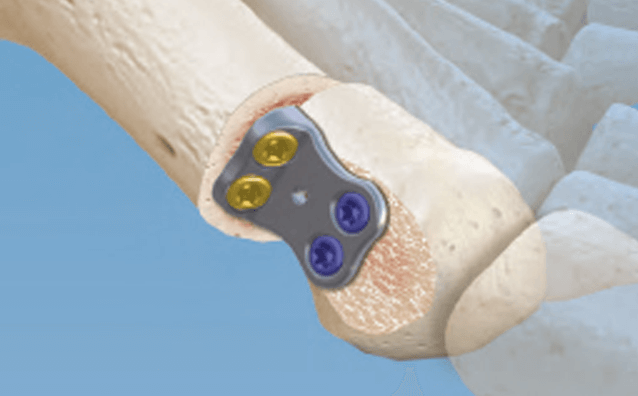

CONMED Foot and Ankle offers tailored innovation and simplified solutions. Explore our complete portfolio of arthroplasty, biologic, fixation, implant, suture anchor, and instrumentation offerings for foot and ankle surgery.

Dr. Early - Deformity Correction Using the Cotton Wedge

Dr. Early - Lateral Column Lengthening Using the Evans Wedge